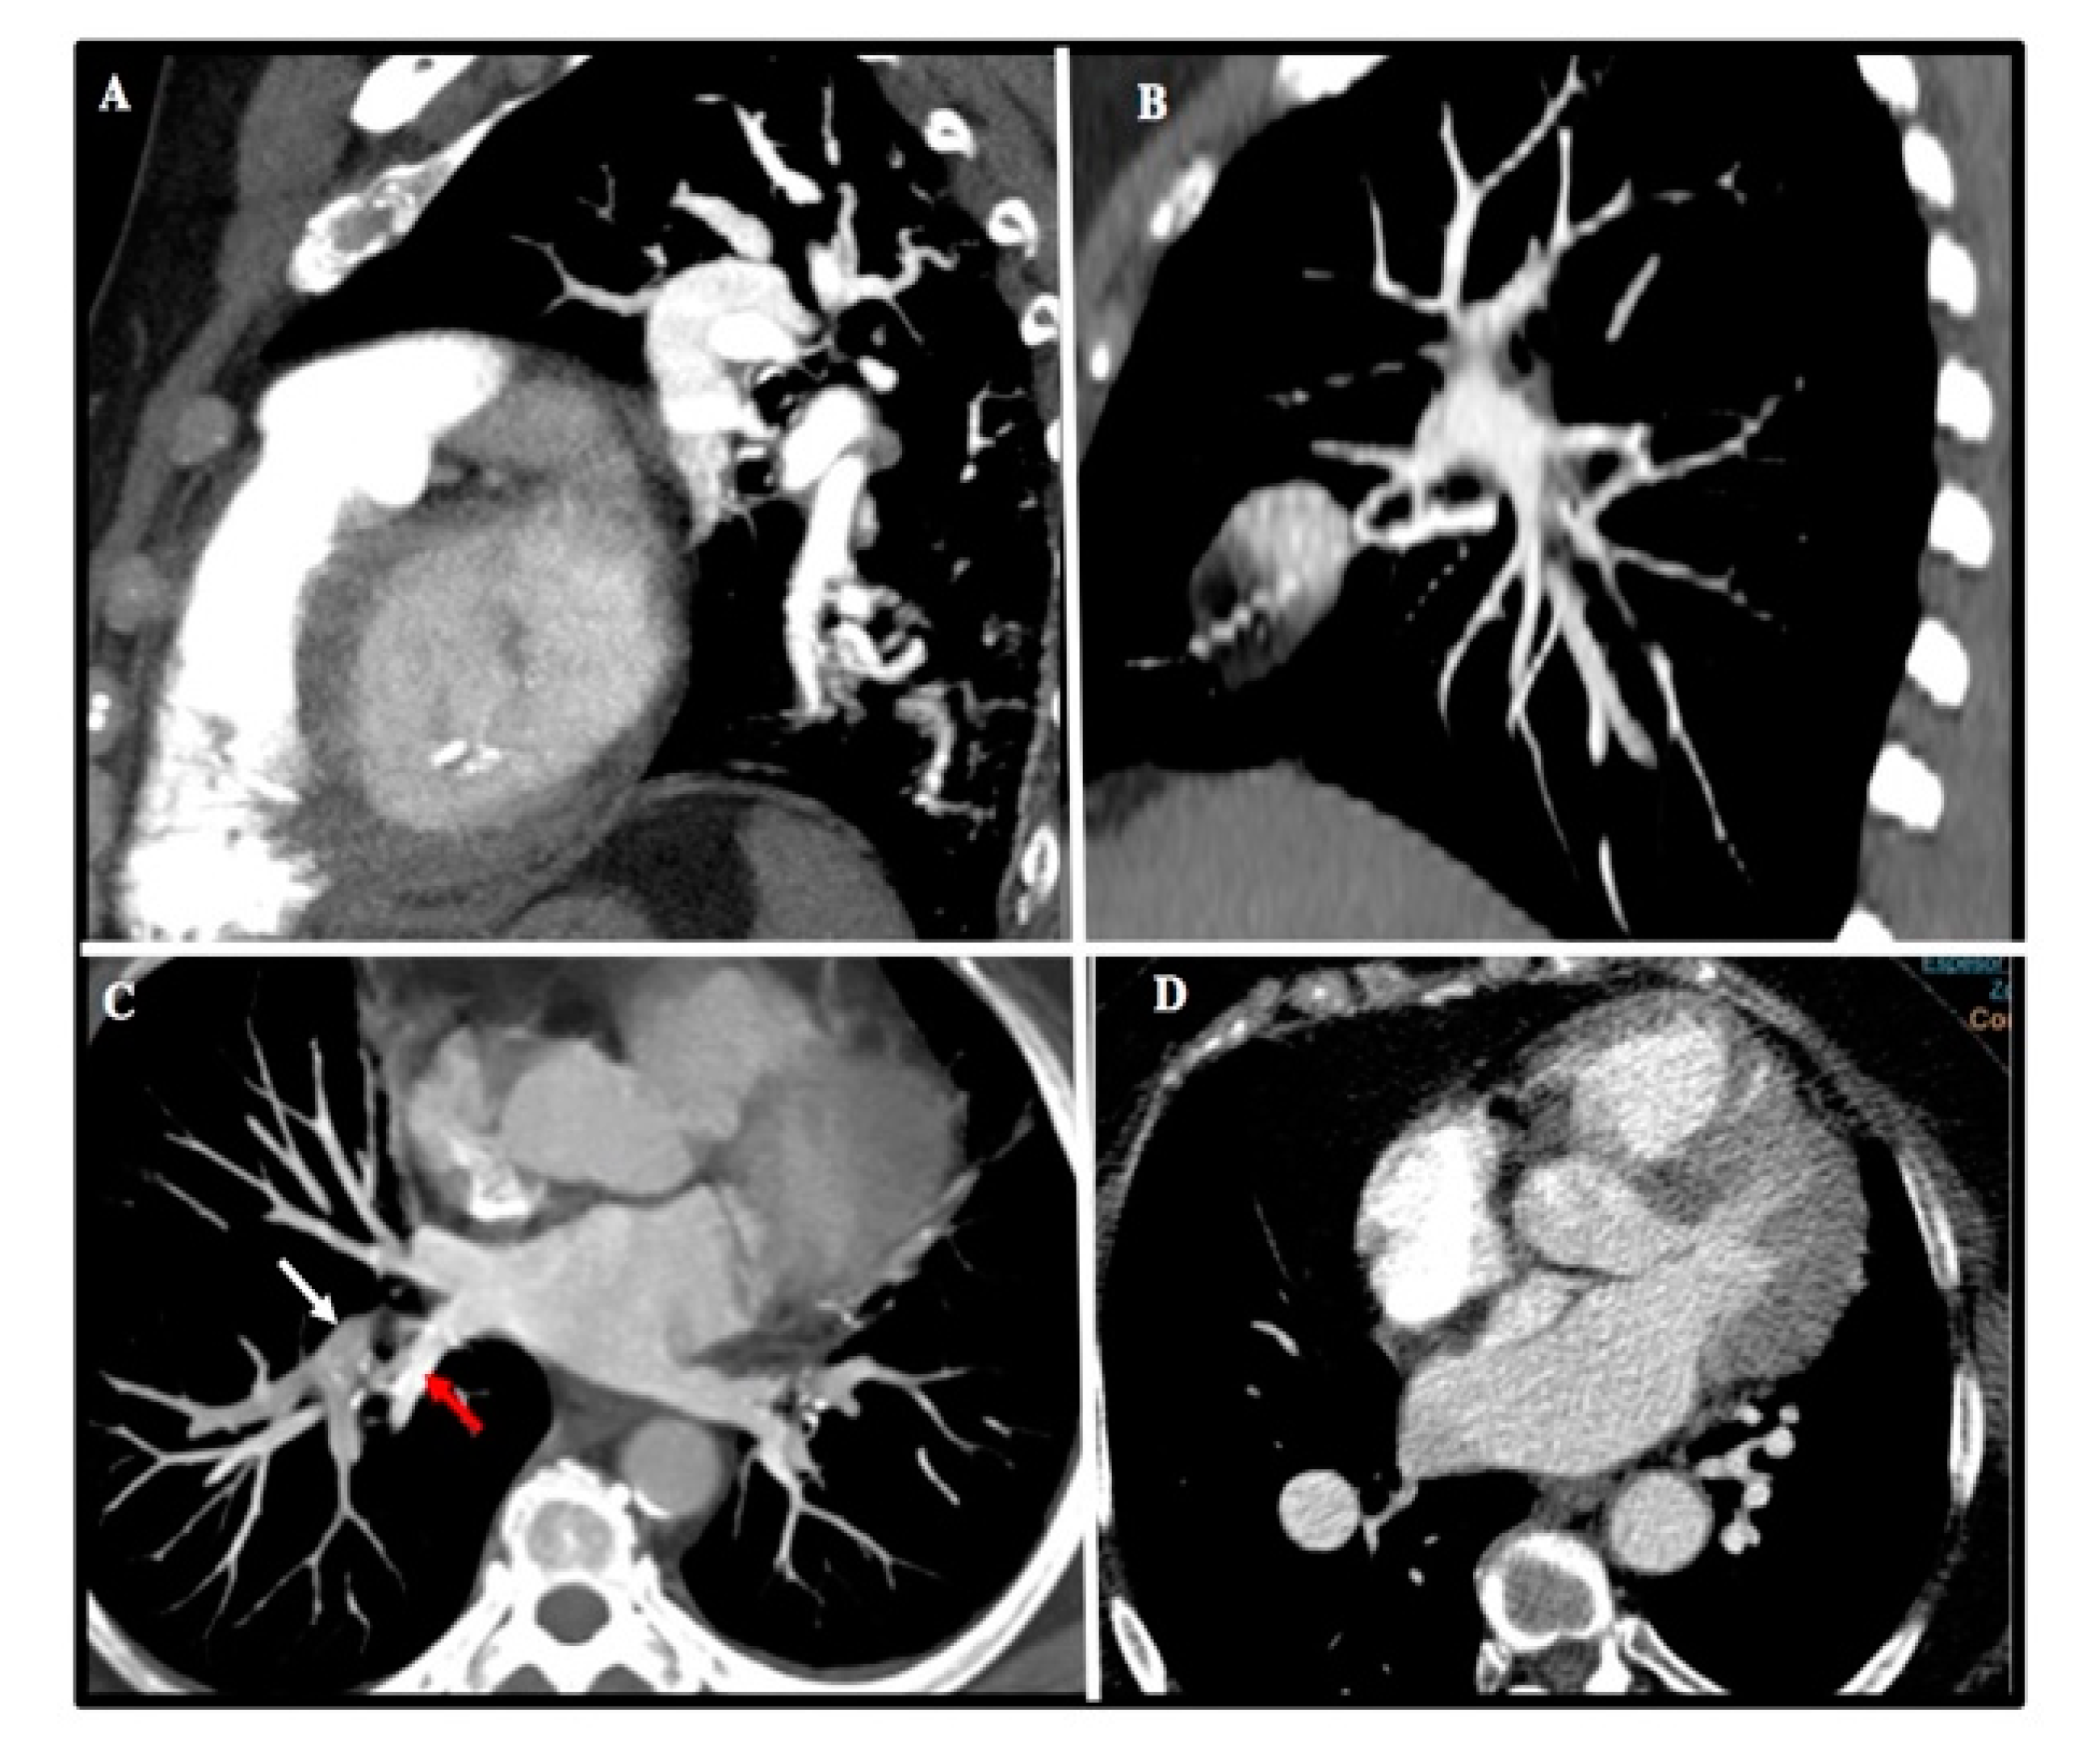

Figure 2.

Common imagen artifacts found in MCTA. (A) Motion artifact at lower lobes. (B) CT stair artifact due to inadequate slice thickness. (C) Suboptimal contrast opacification of right upper lobe artery (white arrow) and inferior right vein (red arrow). (D) CT image noise in an obese patient.

Up to 89% of MCTA studies were considered optimal. The most frequent causes of suboptimal studies were slice thickness greater than 3 mm (38%), poor opacification (25%), respiratory motion artifact (11%), obesity (9%), and improper breath-holding (9%) (Figure 2).